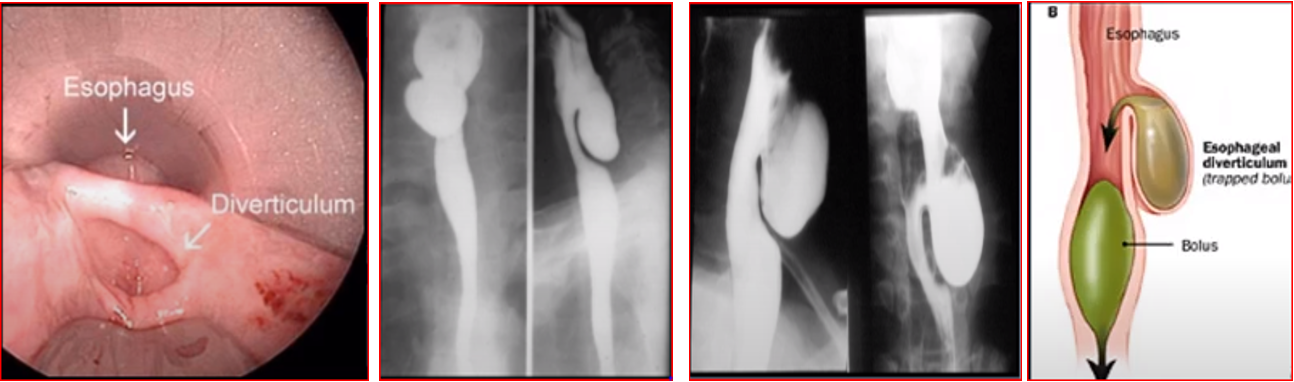

Pharyngeal Pouch- Zenker’s Diverticulum

A laterally placed swelling of the neck located behind the sternomastoid muscle below the thyroid cartilage. It occurs as a result of protrusion or herniation of the mucosa of the pharyngeal wall through the Killian’s dehiscence.

The later is a weak area of the pharyngeal wall between the oblique fibres of thyropharyngeus and the sphincter like transverse fibres of cricopharyngeus part of the inferior constrictor muscle.

Thin Barium Swallow – Evidence of pouch

Esophagoscopy - not indicated - may result in perforation

outpouching

Zenker’s Diverticulum